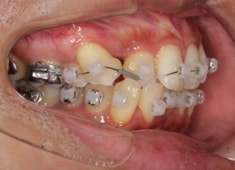

左上3番埋伏歯

治療法:フルパッシブブラケット:T21

治療開始から24ヶ月後